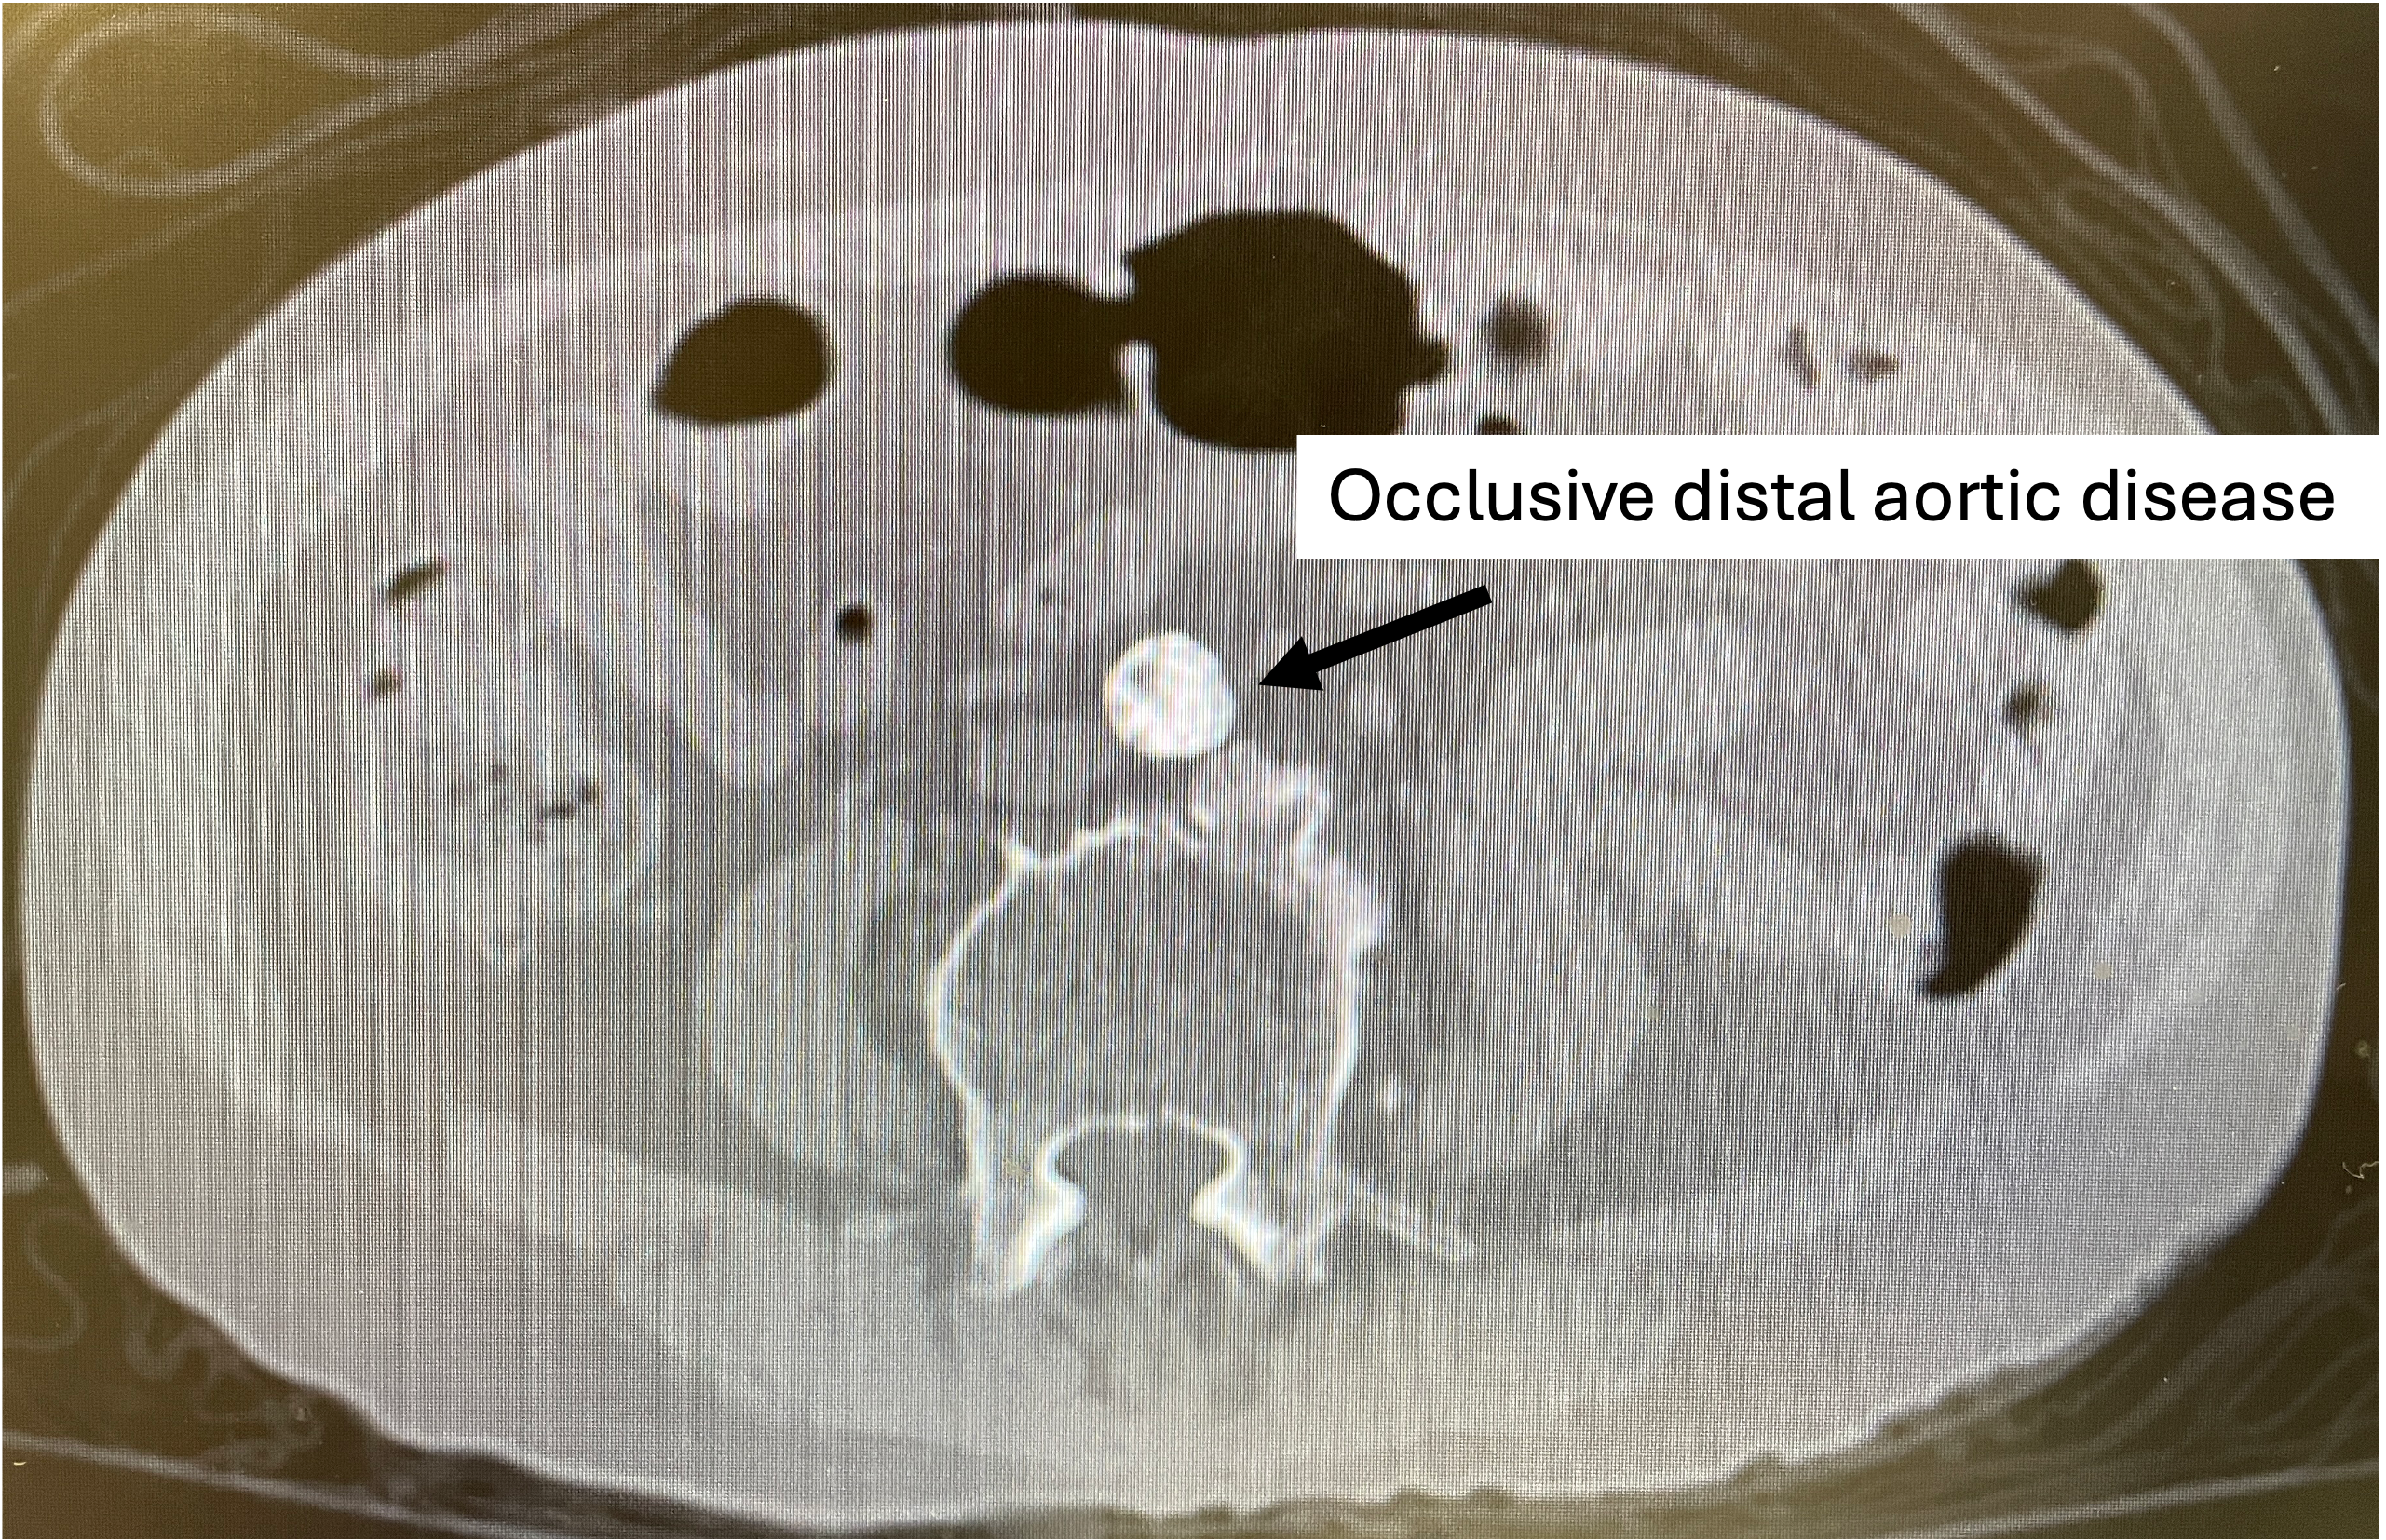

ECG showed RBBB. Haemoglobin was 12g/dL, creatinine 97umol/L, and troponin peaked at 13076ng/L (reference <34). TTE showed severe LV dysfunction (LVEF 25%) with preserved RV function and moderate functional mitral regurgitation. After a period of medical therapy, cardiac MRI showed LVEF improved to 40% with evidence of a previous infarct but viable myocardium. CT showed porcelain aorta and severe aortoiliac disease with occlusions in the infrarenal aorta and bilateral common iliac arteries.

The Vascular team performed aortoiliac revascularisation to concurrently treat his peripheral vascular disease and allow for femoral access for CHIP. Kissing covered stents were placed from the abdominal aorta to bilateral CIAs and EIAs using the ¡°pave and crack¡± technique with chimney stenting to the IMA. After recovery, single access for Impella CP supported high-risk PCI (SHiP) was performed via the left femoral artery with a 7F sheath through the 14F Impella sheath. Intervention began with the LAD using rotational atherectomy (1.25mm burr) but led to hemodynamic instability despite Impella support, requiring emergency intubation and dopamine infusion. Significant blood loss was noted from the SHiP access due to the inadvertent migration of the PCI sheath proximally, and addressed by repositioning the sheath and transfusion. Once stabilised, the LAD, diagonal, and LCx arteries were treated with rotational atherectomy (1.25mm burr). The LCx had follow up orbital atherectomy, and scoring balloon angioplasty for a large ostial calcific nodule. The left main stem bifurcation was treated with drug eluting stents using OCT guided nano crush technique (3.5/28mm LMS-LAD, 3.5/28mm LCx). The first diagonal and mid LCx were treated with drug eluting balloons (2.5/30mm, 2.5/20mm). Final POT was performed in the LMS (4.0/8mm non-compliant at 18atm). Final OCT and angiography showed satisfactory result with TIMI 3 flow.